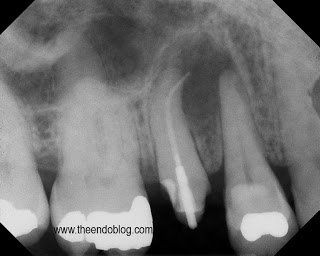

This root canal was done by her general dentist 3 months earlier. As you can see it is overfilled, post placed, crown prepped and ready for new crown, but patient continues to have symptoms with the tooth.